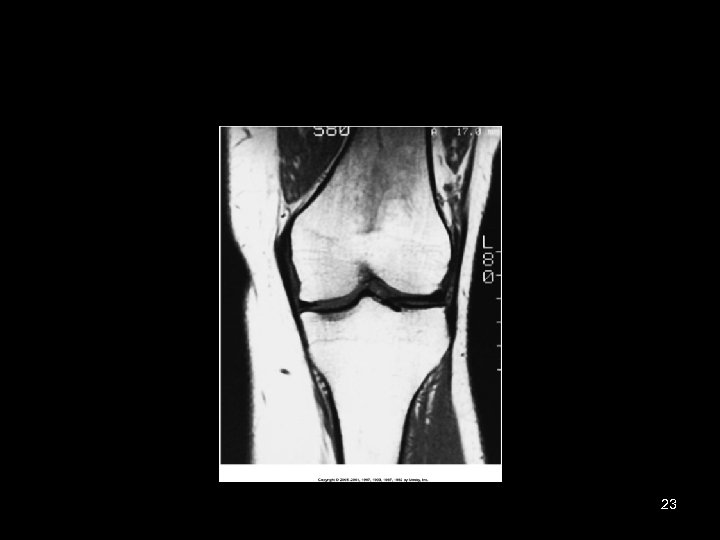

23